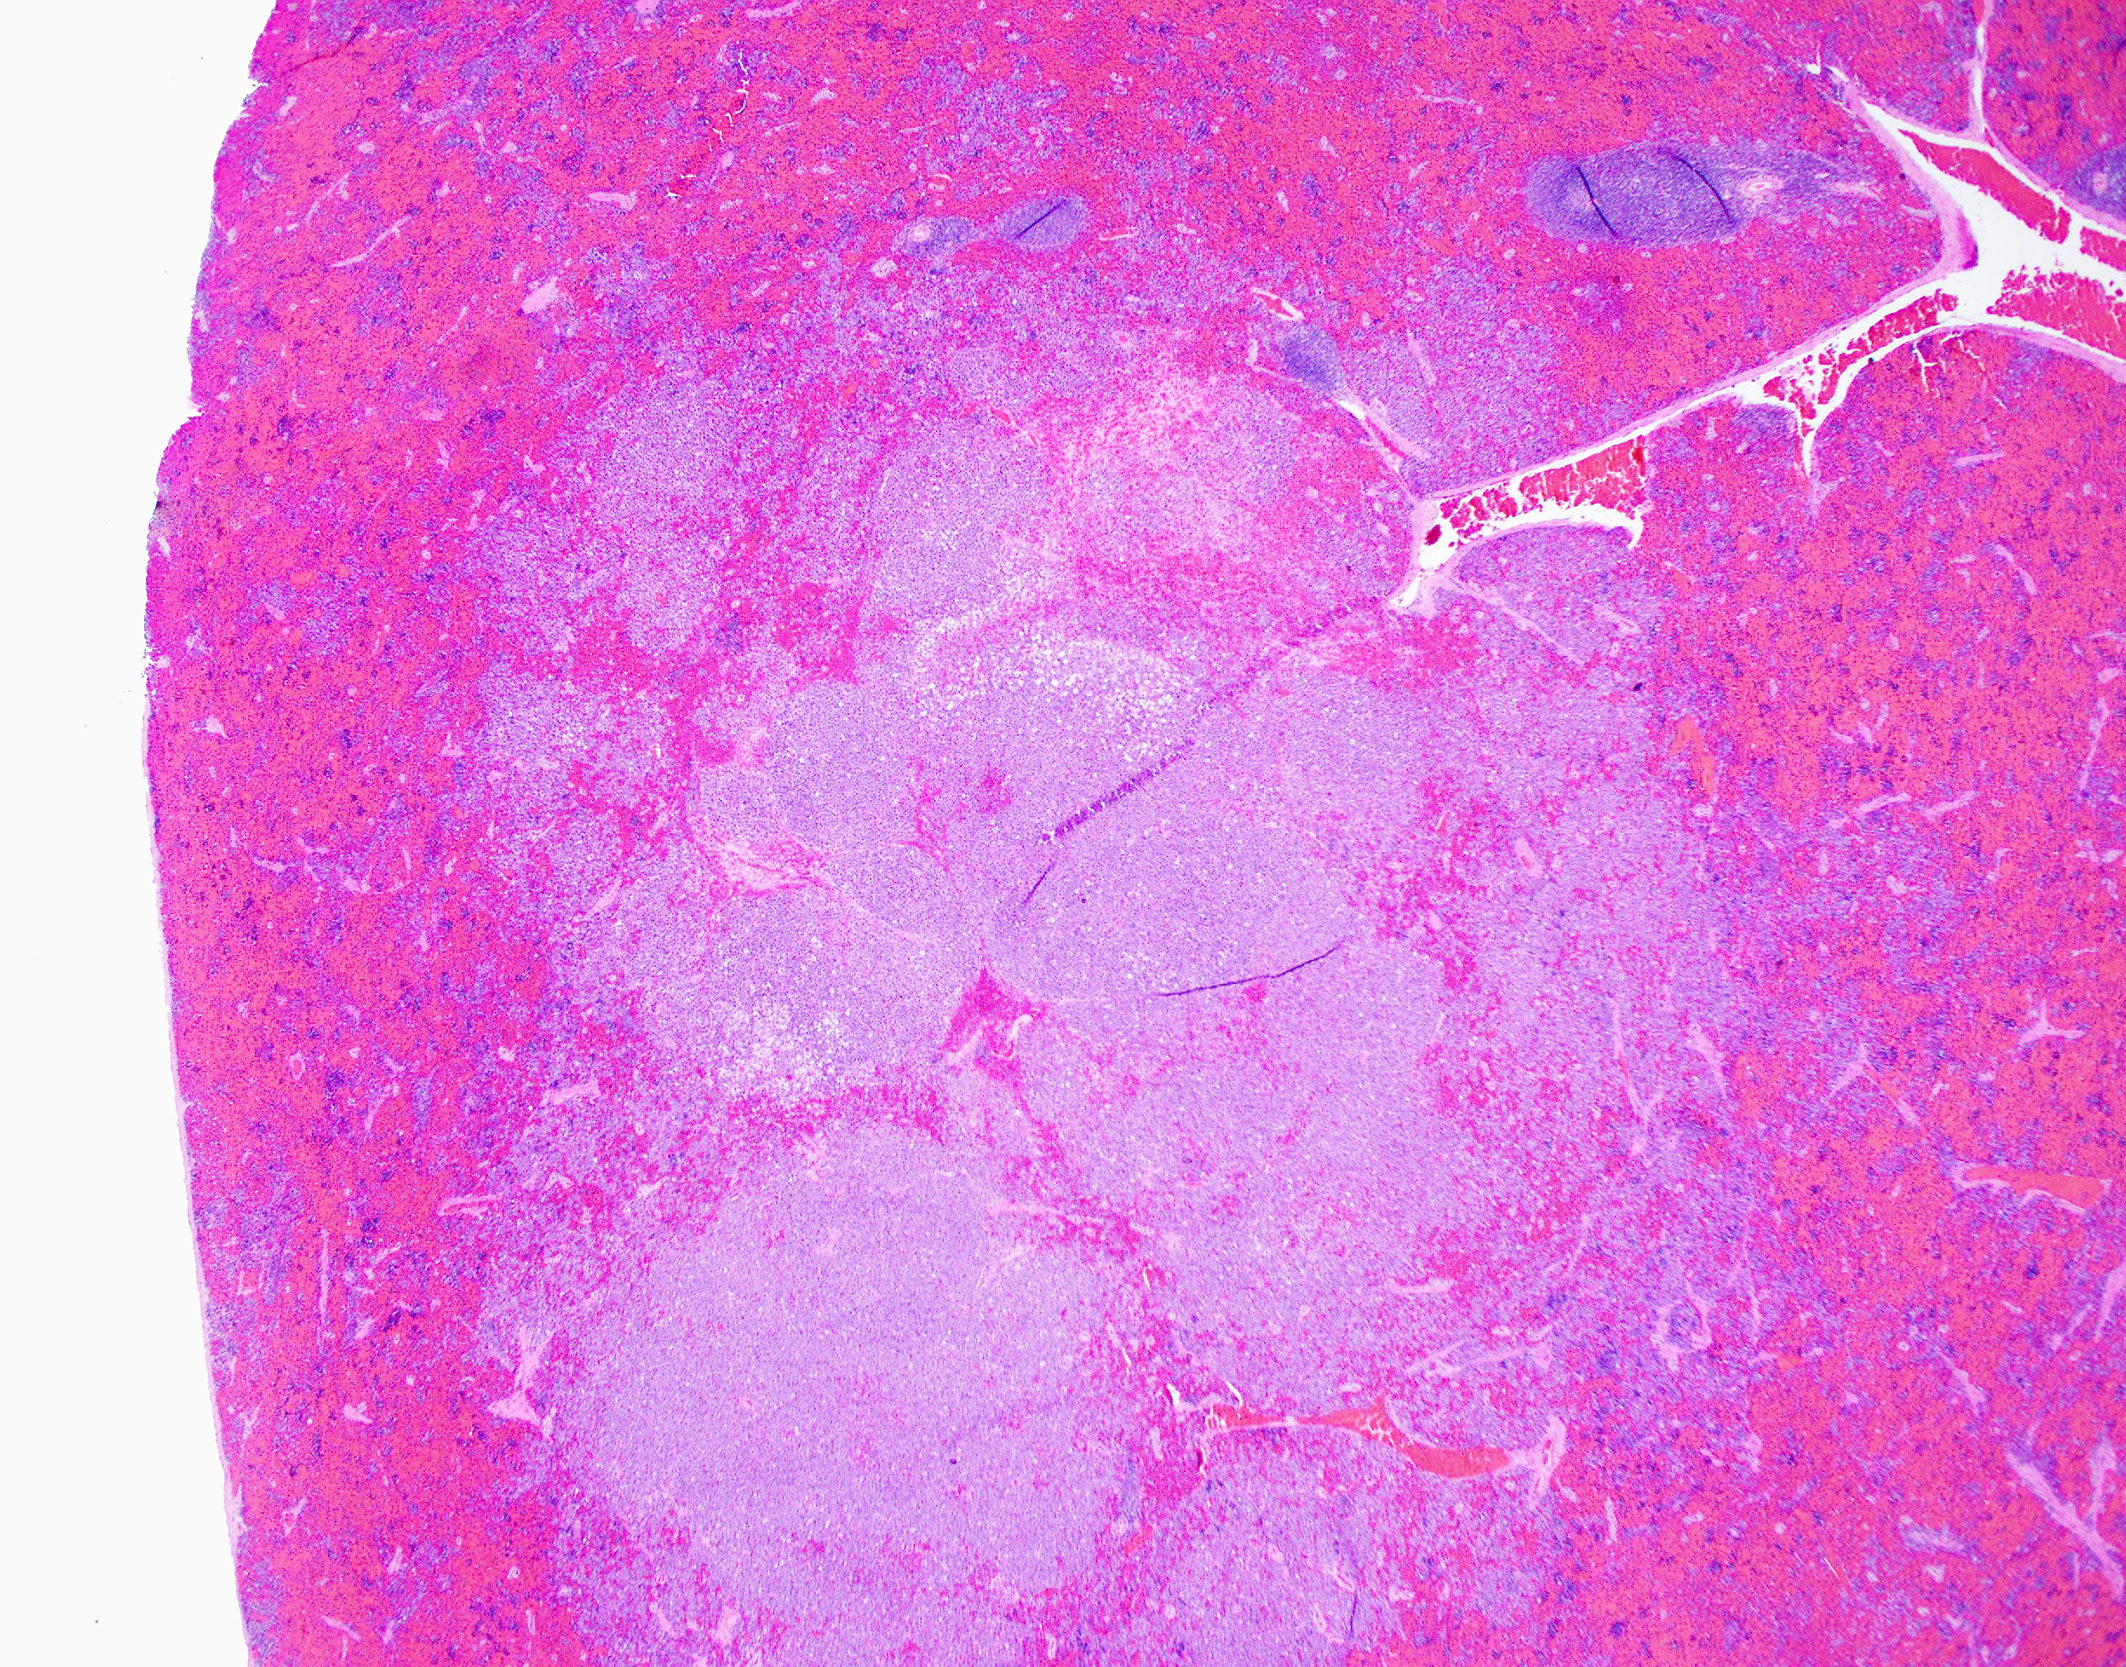

SPLEEN (slide not included):

- Multifocal to coalescing malignant plasma cell tumors (multiple myeloma/plasma cell myeloma), multifocal with atypia [mitotic count = 11 mitotic figures in 10 [40x x FN22] HPF]

- Extramedullary hematopoiesis, chronic, multifocal, moderate

On gross examination of affected bones, the trabecular bone/medullary cavity are replaced and filled by a soft, fleshy to gelatinous, dark red to grey-pink nodules and masses.6,29 Histology shows focal or locally extensive solid tumors of densely packed neoplastic plasma cells arranged in sheets, cords, and packets that replace the hematopoietic cells and adipose tissue of the medullary cavity and are supported by a fine fibrous stoma.6,7,16,29,32 Cortical bone destruction with/or without local soft tissue invasion can be seen.29 Cellular features of plasma cell differentiation include round cells with moderate to large amounts of amphophilic to basophilic cytoplasm with perinuclear clearing (Golgi apparatus).7,9,16,18,22,30,32 Nuclei are paracentral to eccentrically placed with clumped chromatin that aggregate in the center or along the nuclear membrane ("clockface" pattern).7,9,16,18,22,32 Mott cells with prominent cytoplasmic vacuoles (Russel bodies) containing immunoglobulins and may result from altered intracellular protein transport.18,22,32 Due to differences in stain protocols, these vacuoles can range from semi-clear, to light blue, to pink.22,32 "Flame cells" are characterized by an outer rim of densely purple or eosinophilic cytoplasm,32 with light to bright pink projections/blebs or fringe due to accumulation of immunoglobulins.7,22,23,29 Less well-differentiated tumors display a wider range of cellular and nuclear pleomorphism, variable nuclear-to-cytoplasmic ratio, increased numbers of binucleate and multinucleated cells, and lack of Golgi perinuclear clearing.29,32 Plasma cell tumors infrequently have intratumoral light chain amyloid (AL-amyloid).6,7,18,19,22,24,30,32 Erythrophagocytic plasma cell tumors have been described.3,26 With less differentiated forms, immunohistochemistry (IHC) can be useful to rule-out other round cells tumors. In dogs, MUM1 is the most specific marker for plasma cell tumors.6,7,9,16,24,26,31-34 Multiple myeloma oncogene 1 (MUM1) is an interferon regulatory transcription factor involved in immunoglobulin light-chain re-arrangement and production of plasma cells.16,22,24,31,32 Additional tumors that can infrequently be immunoreactive to MUM1 include B-cell lymphoma and anaplastic lymphoma.24,32 Less consistently plasma cell tumors will stain with lambda and kappa light chains, Ig heavy chains, CD79a, and CD20.9,19,22,24,32,33 In one study of canine plasmacytomas, 93.5% of tumors were immunoreactive to MUM1, while only 56.2% and 19.4% of tumors were reactive with CD79a and CD20, respectively.24 In a case series in cats, 32% of MRDs were immunoreactive to CD79+.19 Methyl green pyronine histochemical stain inconsistently highlight plasma cells.9

The gross image of marked a markedly enlarged spleen with multifocal, pale tan nodules prompted a strong reminder from Dr. Alves that this pattern should raise suspicion for necrotizing splenitis across species lines. The marked splenic enlargement in this species is a common finding in older ferrets and typically associated with extramedullary hematopoesis (noted by the contributor in this case).